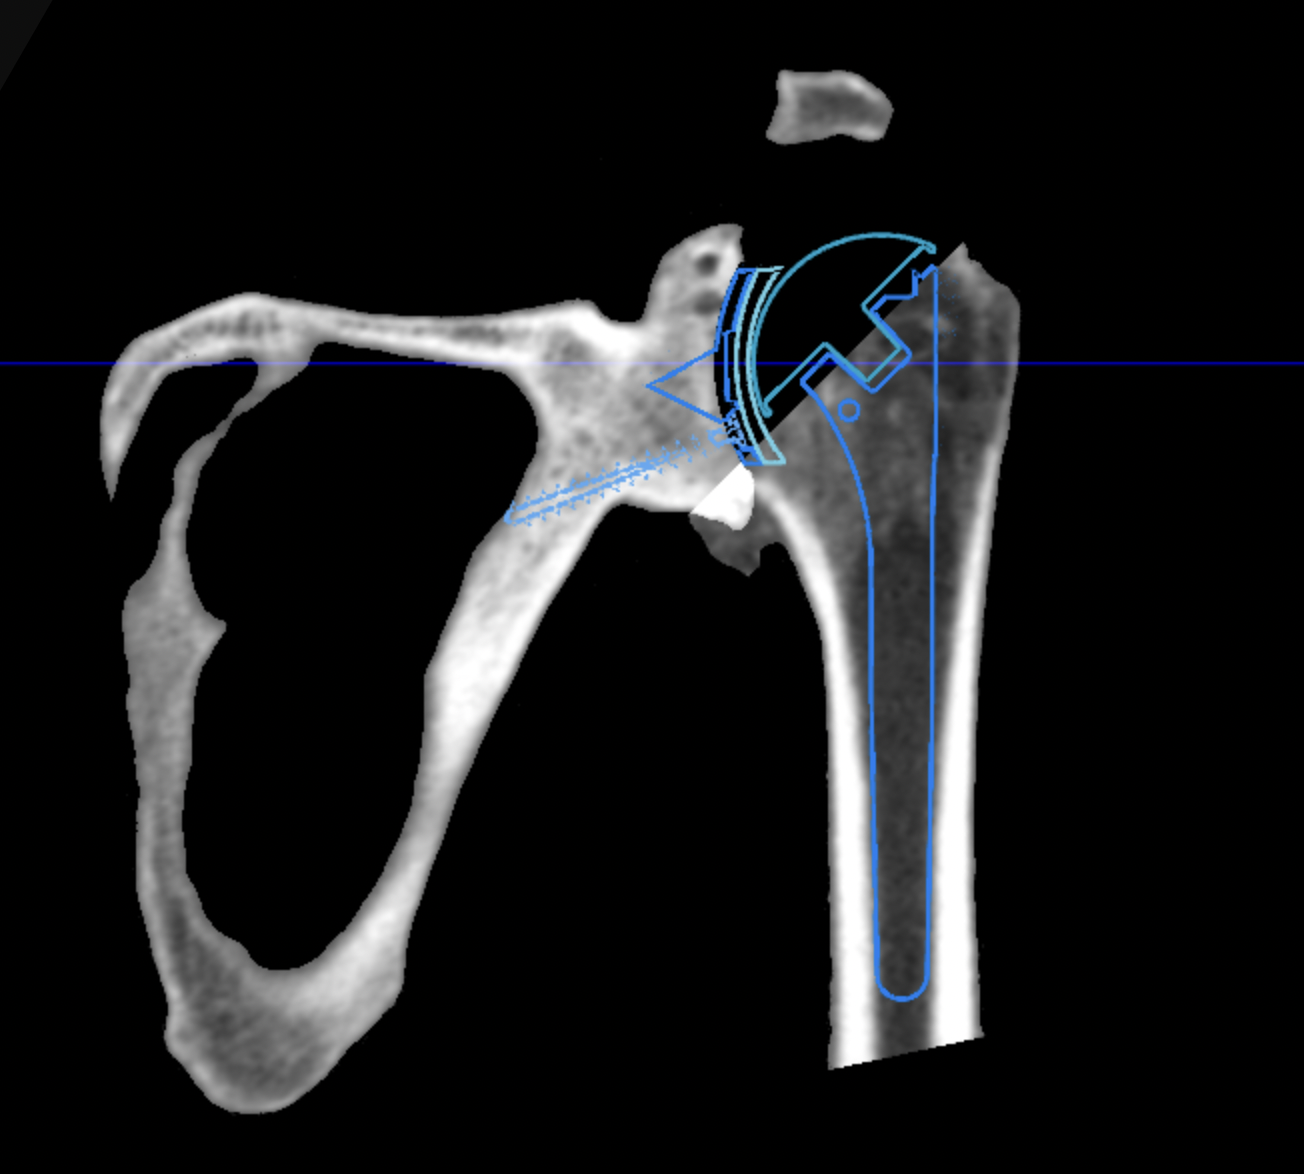

Obecnie istnieją programy komputerowe, które ułatwiają planowanie zabiegów operacyjnych. Procedura ta obejmuje przeprowadzenie tomografii komputerowej chorego stawu ramieniowego przed zabiegiem. Następnie wyniki badania są importowane do specjalnego oprogramowania, które generuje trójwymiarowy model operowanego stawu. Programy te oferują zestaw narzędzi, które umożliwiają precyzyjne zaplanowanie pozycji implantów oraz ich rozmiarów. W znacznym stopniu ułatwiają one przeprowadzenie zabiegu operacyjnego oraz zmniejszają ryzyko popełnienia błędu.

Obecnie technologia medyczna stale się rozwija. Niektóre firmy integrują planowanie z samym zabiegiem operacyjnym. Oznacza to, że podczas zabiegu ortopeda jest prowadzony przez system nawigacyjny wspomagany komputerowo. Jednakże, jeśli chodzi o protezy stawu ramieniowego, według mojej oceny, są one wciąż uznawane za produkt jeszcze nie do końca doskonały.